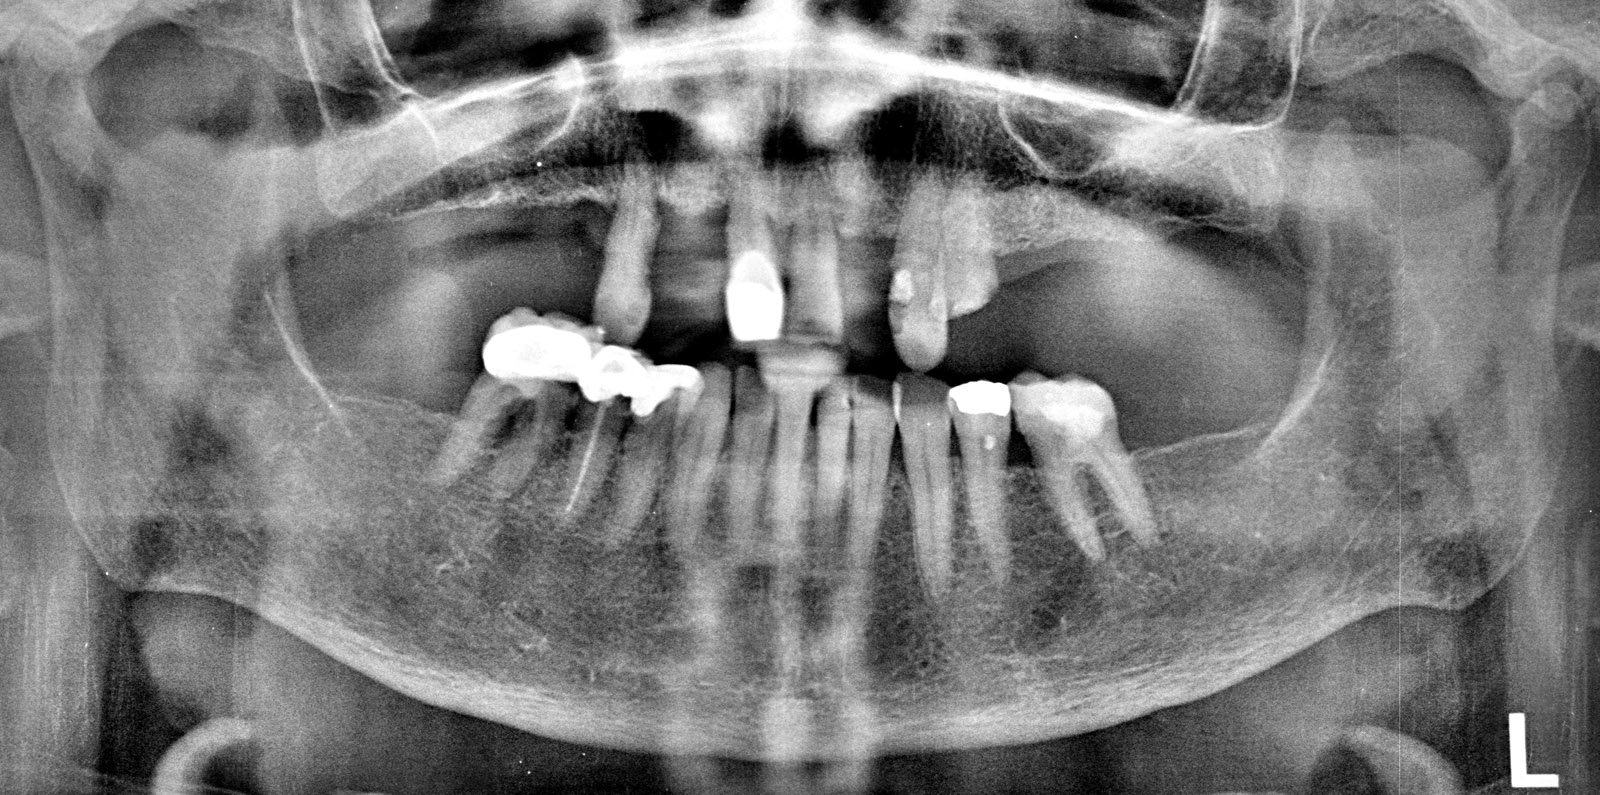

The OPG radiograph confirmed the absence of any pathology in both jaws and the presence of large maxillary sinuses, with inadequate bone volume below them for the placement of dental implants in these regions, without sinus grafts (Figure 3). The patient was very reluctant to undergo any sinus grafting procedures.